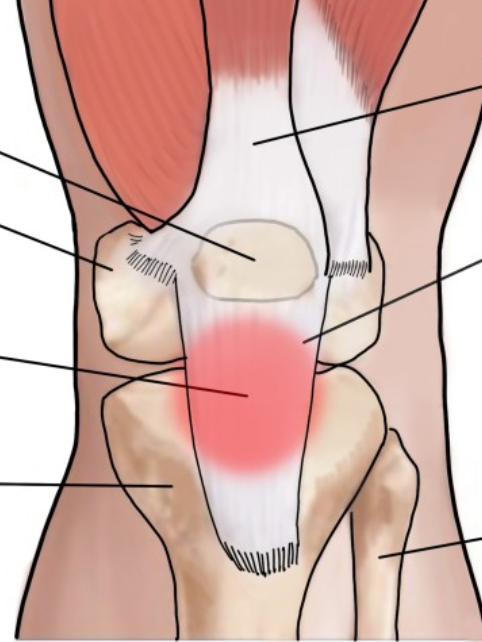

인대와 건은 역할은 달라도 근골격계의 중요한 요소들입니다. 근육을 공부할 때 인대와 건은 꼭 같이 알아두어야 해요. 이 친구들 중 하나라도 문제가 생기면, 우리 몸의 움직임이나 안정성에 큰 영향을 미칠 수 있습니다. 보통 인대와 건을 구분할 때 뼈와 뼈를 이어주면 인대, 근육과 뼈를 이어주면 건이라고 하는데, 제가 지금 이야기한 기능을 바탕으로 이해하는 것이 더 합리적입니다. 예를 들어 문제를 내볼게요. 아래 그림에서 슬개골(patella)과 경골(tibia)을 이어주고 있는 조직은 인대일까요, 건일까요?

img.png

대부분의 친구들은 아마 인대라고 답했을 거예요(실제 수업시간에 물어보면 대부분 인대라고 대답하거든요). 슬개골(patella)이라는 뼈와 경골(tibia)이라는 뼈를 이어주고 있으니까 인대라고 생각했을 거예요. 그런데, 슬개골은 종자뼈, 혹은 건내뼈라고해요. 바로 건(tendon)의 내부에 존재하는 뼈라는 뜻입니다. 그러니, 저 슬개인대, 혹은 슬개건이 슬개골과 경골을 이어준다기보다는, 대퇴근건의 중간에 끼어서 있을 뿐이라고 보는 것이 합리적입니다.

그래서, 의사들은 여기에 생긴 염증, 손상을 슬개건염(patellar tendinitis)이라고 하지, 슬개인대염(patellar ligamentitis)이라고는 하지는 않습니다. 이 조직이 하는 역할이 허벅지 앞쪽의 근육, 대퇴사두근(quadriceps femoris)의 수축을 경골(tibia)에 전달하는 역할을 하기 때문입니다. 기능적인 면에서 건이라고 부릅니다..

하지만, 해부학 시간에는 이 부위를 슬개건(patellar tendon)이라고 하기도 하고 슬개인대(patellar ligament)라고 하기도 합니다. 뭐, 양쪽 다 틀린 말은 아닙니다만, 인대와 건의 구분이 그 기능에 따라 정해진다는 사실은 꼭 기억하시기 바랍니다.. 왜냐하면, 이 기능의 차이에 따라 손상의 기전(어떻게 그 부위가 손상되는지), 치료 방법 등이 모두 달라지기 때문입니다. 일단 이야기 나온 김에 슬개골에 대해서도 알아보지요.